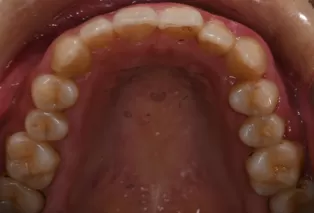

Intraoral photos after treatment